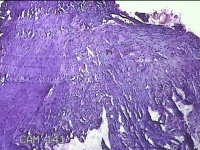

右侧卵巢囊肿

性别

女

年龄

36岁

临床诊断

一般病史

发现双侧附件囊肿1年。

标本名称

大体所见

灰白暗红色囊壁样组织2.5x2x0.3cm一块,表面光滑,部分已切开,囊内容物已流失,囊壁厚0.2cm。

考虑:子宫内膜异位囊肿。